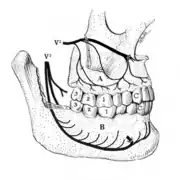

Disorders of the maxillary sinus can be referred to the upper back teeth. The posterior, middle and anterior superior alveolar nerves are all closely associated with the lining of the sinus. The bone between the floor of the maxillary sinus and the roots of the upper back teeth is very thin, and frequently the apices of these teeth disrupt the contour of the sinus floor. Consequently, acute or chronic maxillary sinusitis can be perceived as maxillary toothache,[39] and neoplasms of the sinus (such as adenoid cystic carcinoma)[40]: 390 can cause similarly perceived toothache if malignant invasion of the superior alveolar nerves occurs.[41]: 72 Classically, sinusitis pain increases upon Valsalva maneuvers or tilting the head forward.[42]

A tooth is composed of an outer shell of calcified hard tissues (from hardest to softest: enamel, dentin, and cementum), and an inner soft tissue core (the pulp system), which contains nerves and blood vessels. The visible parts of the teeth in the mouth – the crowns (covered by enamel) – are anchored into the bone by the roots (covered by cementum). Underneath the cementum and enamel layers, dentin forms the bulk of the tooth and surrounds the pulp system. The part of the pulp inside the crown is the pulp chamber, and the central soft tissue nutrient canals within each root are root canals, exiting through one or more holes at the root end (apical foramen/foramina). The periodontal ligament connects the roots to the bony socket. The gingiva covers the alveolar processes, the tooth-bearing arches of the jaws.[45]: 1–5